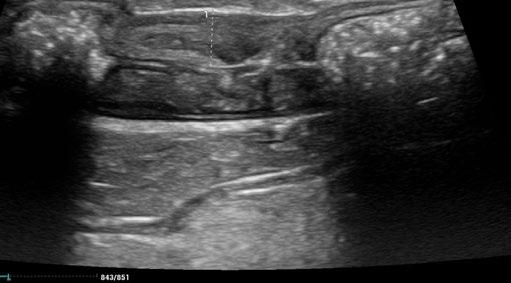

A repeat ultrasound after 10 days of treatment indicated early evidence of a reduction of the colonic lesion.

We planned to provide 42 days of treatment and serially assess the lesion by ultrasound to determine the effect of the treatment.

Here are the sequential images:

At the time of writing, 1 month after completion of a 42 day course of medication, Cha Cha is asymptomatic, with no clinical, clinical pathological, or sonographically detectable signs of disease. This response is very difficult to attribute to anything other than highly effective treatment of focal, colonic ‘dry’ FIP with GS-441524.